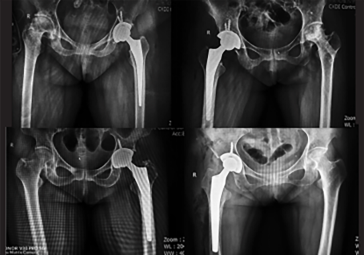

在傳統(tǒng)全髖關(guān)節(jié)置換術(shù)中,假體位置不良是手術(shù)失敗的主要原因之一。 機(jī)器人 輔助全髖關(guān)節(jié)置換術(shù)提高了髖臼杯植入位置的準(zhǔn)確性,降低手 術(shù)失敗率,提高患者術(shù)后滿意度。

in-1.png

假體安裝角度誤差

所有機(jī)器人輔助髖關(guān)節(jié)置換術(shù)髖臼杯的外展角和前傾角誤差在 1°以內(nèi)。

in-2.png

術(shù)后雙下肢長(zhǎng)度差異

所有機(jī)器人輔助髖關(guān)節(jié)置換術(shù)患者術(shù)后雙下肢長(zhǎng)度差異在5mm 以內(nèi)。

in-3.png

術(shù)后住院時(shí)間

所有機(jī)器人輔助髖關(guān)節(jié)置換術(shù)后患者,均在術(shù)后一周內(nèi)出院,80% 的患者可以不拄拐獨(dú)立行走。

in-4.png

術(shù)后脫位情況

所有機(jī)器人輔助髖關(guān)節(jié)置換術(shù)后患者,術(shù)后三個(gè)月隨訪 0 脫位,功能恢復(fù)良好,Harris 評(píng)分優(yōu)于傳統(tǒng)全髖關(guān)節(jié)置換術(shù)。

資料來(lái)自于西安大學(xué)第二附屬醫(yī)院